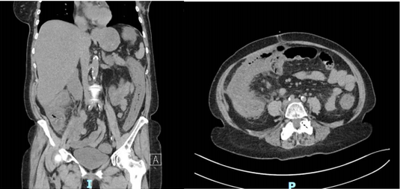

Mulher, 64 anos de idade, se queixa de dor abdominal difusa de forte intensidade há 24 horas, acompanhada de febre e diarreia sem sangue. Nega sintomas urinários. Antecedente de internação prévia há 1 mês devido a pneumonia. Refere tabagismo. Tem hipertensão arterial sistêmica e diabete melito, controlados com medicamentos. Ao exame físico: Regular estado geral, FC:110 bcp, FR: 16, PA: 100x70 mmHg; Ausculta torácica sem alterações. Abdome distendido, doloroso com sinais de irritação peritoneal difusamente. Exames bioquímicos: Hb: 11,3 g/dL; Leuco: 19,57 mil/mm³; PCR: 60mg/dL; Creat: 2,19 mg/dL; Ureia: 141 mg/dl; Lactato: 28 mg/dL; Gasometria sem outras alterações; Tomografia de abdome:

Qual é a principal hipótese diagnóstica?